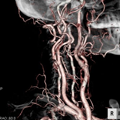

脳血管造影(正面・側面)

脳血管3D造影

X線血管造影検査は、カテーテルという細い管を血管内に入れ、造影剤を流すことによって、頭・心臓・腹部・下肢などの血管の走行や形態などを調べる検査です。

また、検査だけでなく、脳梗塞で血栓によって血流が途絶えた血管に対して血栓を回収・吸引して再開通させる治療や、心筋梗塞などで狭くなった心臓の血管に対してバルーンやステントを用いて血管を広げる治療、下肢血管の治療なども行っています。

当院では、2024年1月に導入したバイプレーン装置(ARTIS icono D-spin:SIMENS社製)と既存のデュアルプレーン装置(Infinix Celeve-i:Canon社製)の2台体制で運用しています。

新規導入したバイプレーン装置は、従来機と比べ画像処理能力が格段に上がり、カテーテルなどのデバイスの視認性が向上しています。

また正面・側面のCアームを同時可動することで撮影時間や回数を大幅に短縮できます。

さらに、より高精細な3D画像を得られることで、これまで以上に質が高く安全な治療につなげることができます。

また、患者さんの体格に応じて装置が自動的に線量を制御することで、常に適正線量での透視や撮影が行えるため、患者さんの放射線被ばくを大幅に低減することができます。

安全・利便性の高い装置を設備し、医師・医療スタッフが協力することで、さらに質の高い医療を提供してまいります。